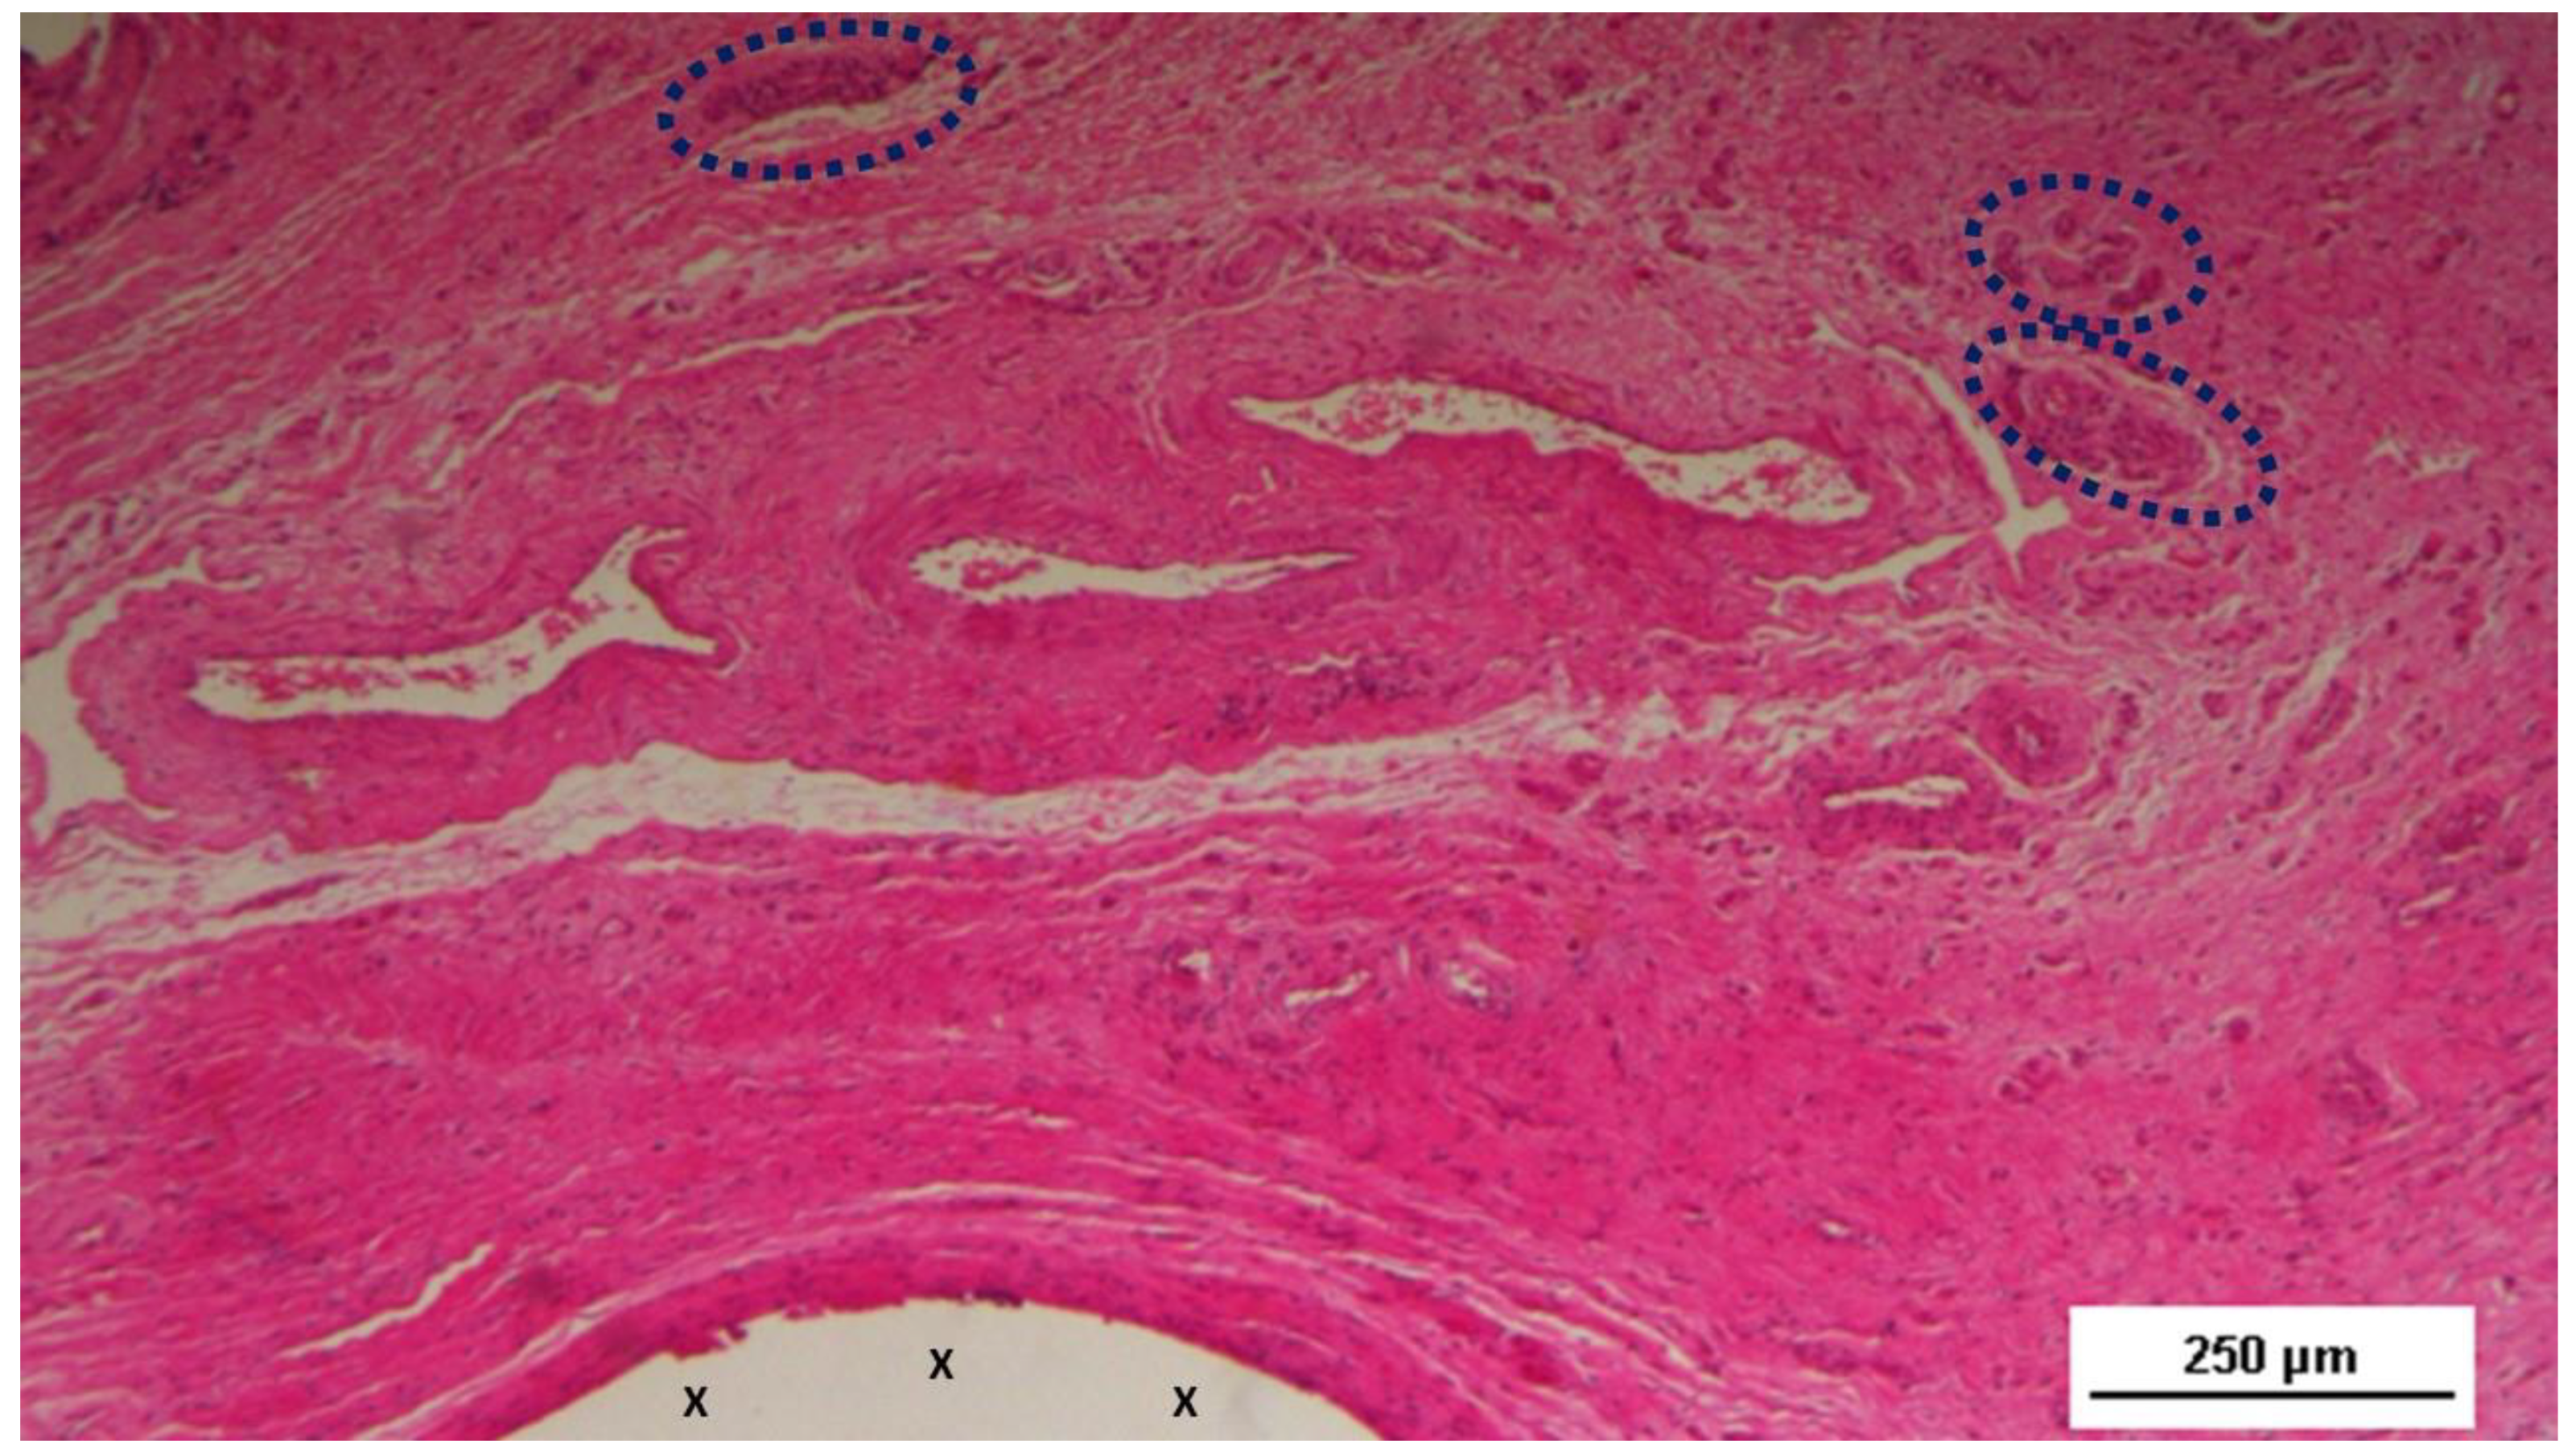

Figure 11. - Biopsy sample excised from the 3D scaffold of the S&S device 6 months post-implantation: In this low magnification microphotograph, two nervous elements (blue circles) are visible between the fabric of the S&S Hernia System (X) and near large, mature arterial structures. HE 25X.